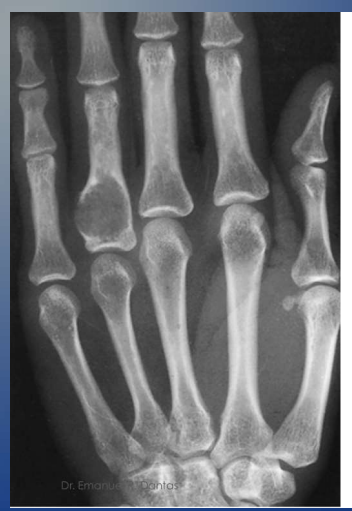

O encondroma é o tumor ósseo mais comum de quais ossos?

Ossos tubulares das mãos